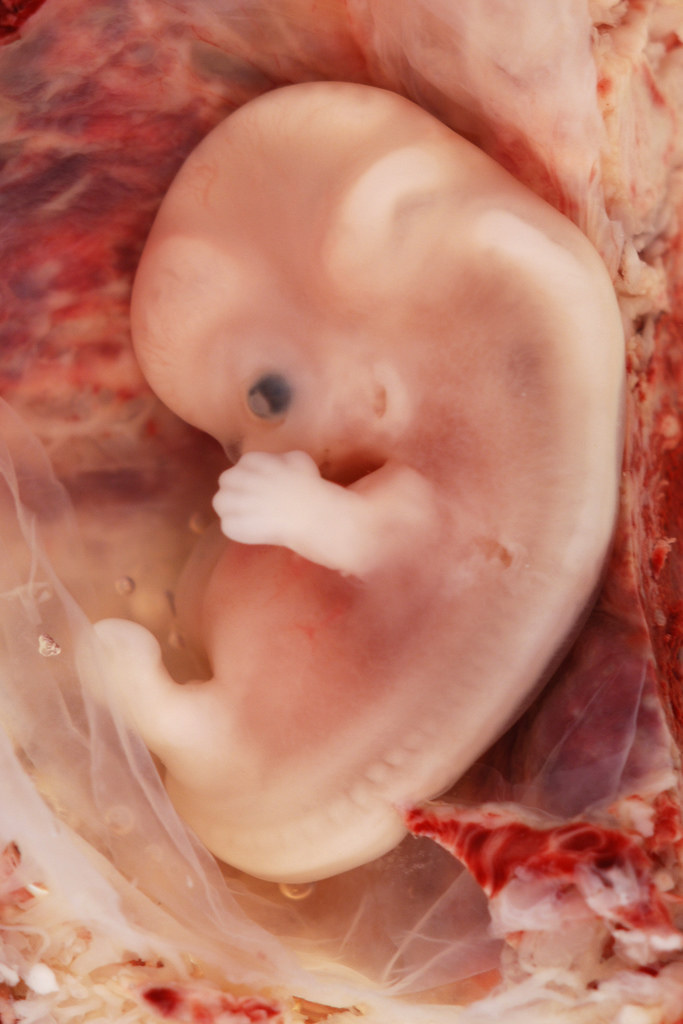

W ciągu 13 tygodni Twoje dziecko zmienia się z mikroskopijnej komórki w płód wielkości brzoskwini. Kształtują się wszystkie główne narządy – serce, mózg, płuca, nerki.

- Z mikroskopijnej komórki jajowej → w zarodek → w embrion → w płód wielkości brzoskwini

- Kształtują się wszystkie główne narządy (serce, mózg, płuca, nerki)

- Pojawia się twarz, rączki, nóżki, paluszki

- Zaczyna bić serce (około 6. tygodnia!)

- Dziecko ma już wszystkie układy – teraz będzie je doskonalić przez kolejne miesiące

Ten proces nazywa się organogenezą – tworzeniem narządów. Dlatego pierwszy trymestr to kluczowy moment dla prawidłowego rozwoju dziecka.

Dziecko zaczyna wyglądać coraz bardziej jak człowiek! Pojawiają się paluszki u rączek i nóżek, rysy twarzy są wyraźniejsze. Wszystkie główne narządy są już ukształtowane – teraz będą dojrzewać. Zarodek oficjalnie staje się embrionem.

→ Przeczytaj: 8 tydzień ciąży – objawy i rozwój dziecka